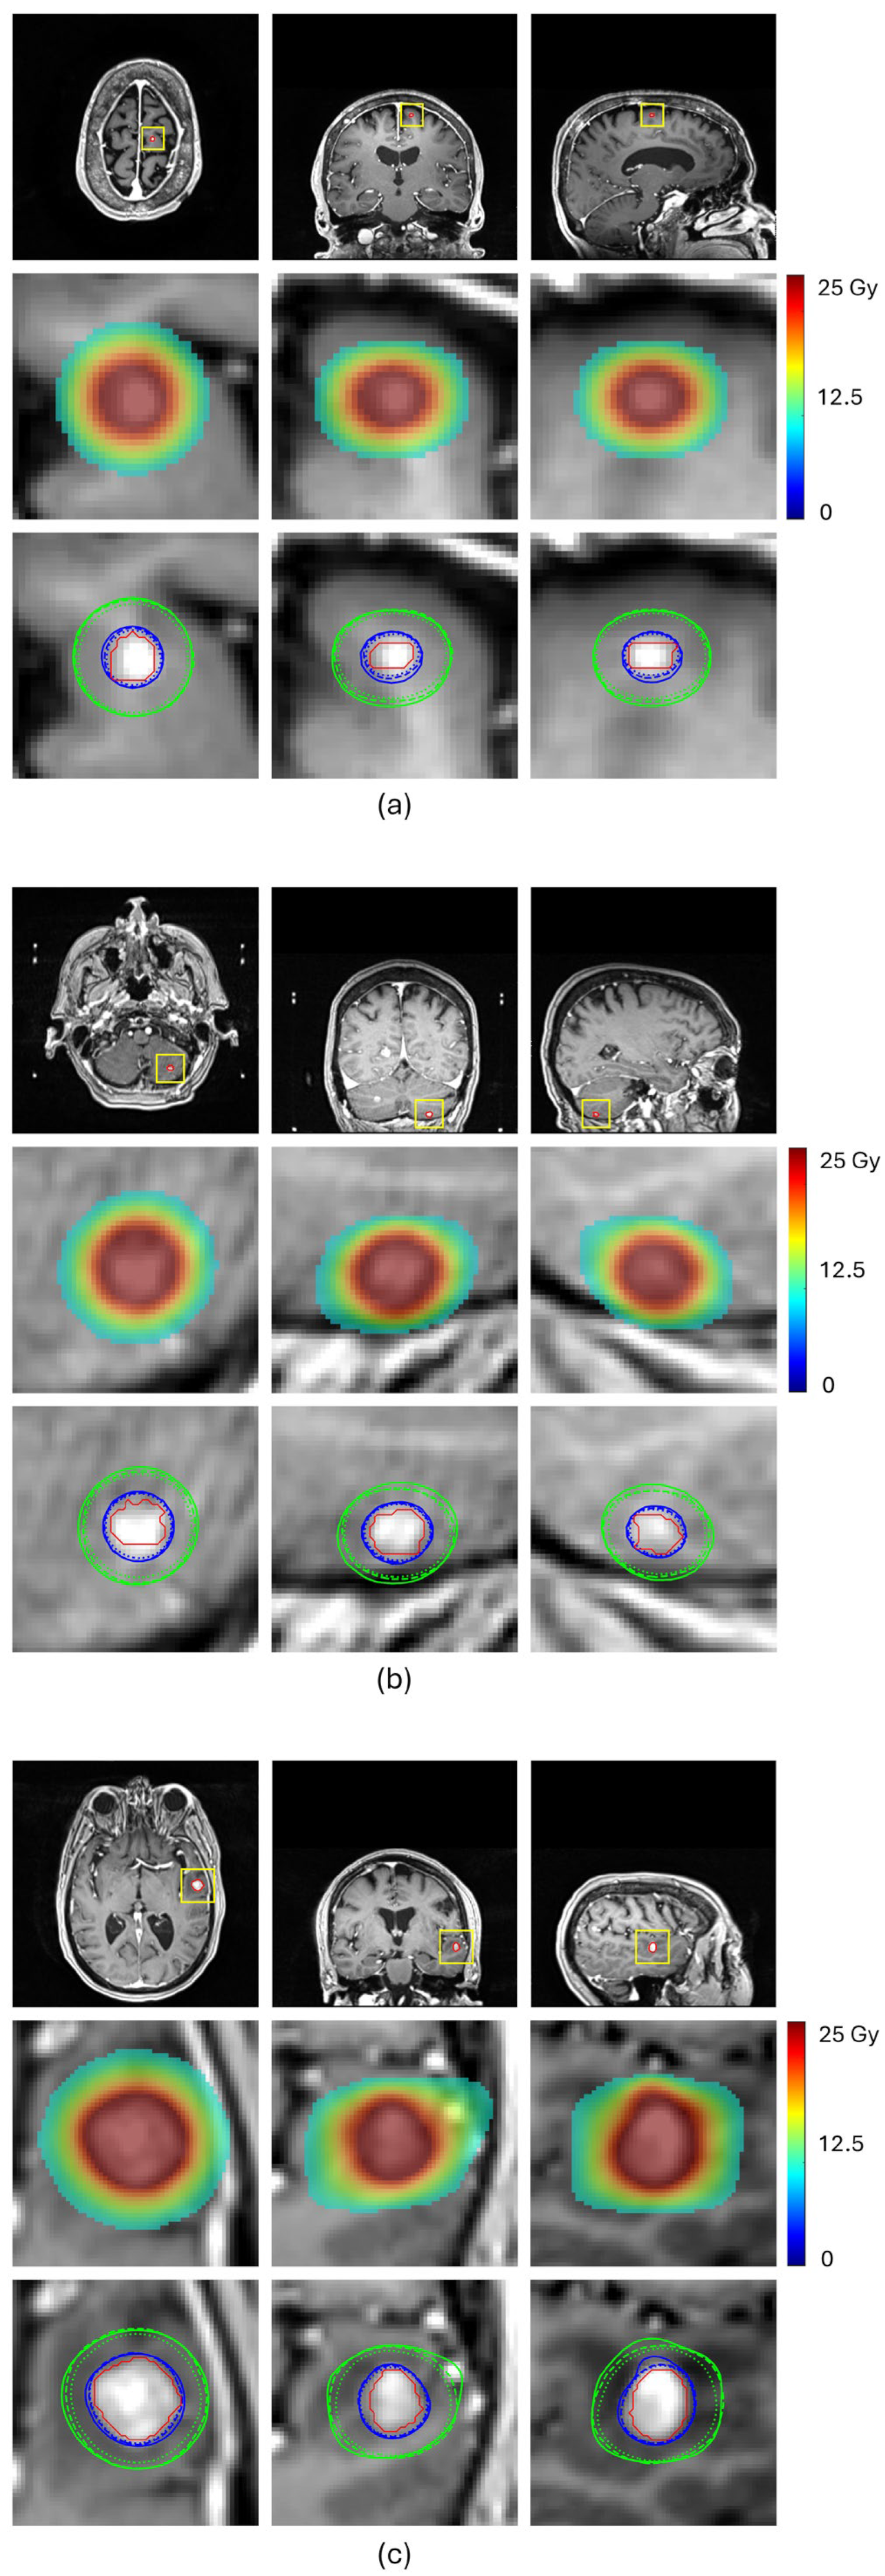

Table 2 and Figure 4 compare the prediction performance of our proposed method with a baseline HD-U-Net trained using the conventional MSE loss for four representative BMs, each selected from a different volume group. For the two small-volume BMs, BM 1 and BM2, our method achieved substantially higher DSC values for both 100% and 50% isodose lines (DSC100%: 0.908 vs. 0.790 for BM1 and 0.936 vs. 0.886 for BM2, DSC50%: 0.947 vs. 0.849 for BM1 and 0.908 vs. 0.827 for BM2), indicating markedly improved agreement with the ground truth dose distribution (Figure 4a,b). These gains translated into significant improvements in plan quality prediction. Selectivity error decreased from 0.19 to 0.06 for BM1 and from 0.11 to 0.06 for BM2, CI50 error reduced from −5.04 to −1.55 for BM1 and from −3.05 to −1.75 for BM2, and GI error from 0.91 to 0.56 for BM1 and from −0.53 to −0.27 for BM2. For the mid-volume BM3, while the baseline mode already produced reasonable similarity in the 100% isodose line, our method further improved the DSC value from 0.926 to 0.944, reducing selectivity error from 0.10 to 0.06. More notably, our method significantly increased the DSC value of the 50% isodose line from 0.847 to 0.925, consistent with the isodose lines shown in Figure 4c, reducing CI50 error from −1.25 to −0.40. With both isodose lines improved, the GI error decreased from −0.48 to −0.01. For the large-volume BM4, both methods achieved comparable similarity for the 100% isodose line (DSC100%: 0.952 vs. 0.951), while our method produced a higher DSC for the 50% isodose line (DSC50%: 0.951 vs. 0.912), as illustrated in Figure 4d. This improvement translated to a decrease in the CI50 error from −0.50 to 0.25 and the GI error from −0.63 to less than 0.01. These results demonstrate that our proposed method consistently enhances similarity of the 100% and 50% isodose lines of the predicted doses relative to those of ground truth doses, especially for small-volume lesions, leading to more accurate prediction of plan quality metrics.

Figure 4. Subfigures (ad) show the predicted results for the four representative BMs, respectively. In each subfigure, the first row displays MRI images in transverse, coronal and sagittal views, with the BM contour outlined in red; The second row presents a zoomed-in view of the BM region (as indicated by the rectangle in the first row), showing the ground truth dose distribution in color wash; The third row compares 100% isodose lines (yellow) and 50% isodose lines (green) from the ground truth dose distribution (solid lines), the dose predicted by the HD-U-Net trained with conventional MSE loss (dotted lines), and the dose predicted by the HD-U-Net model trained with our proposed method (dashed lines).